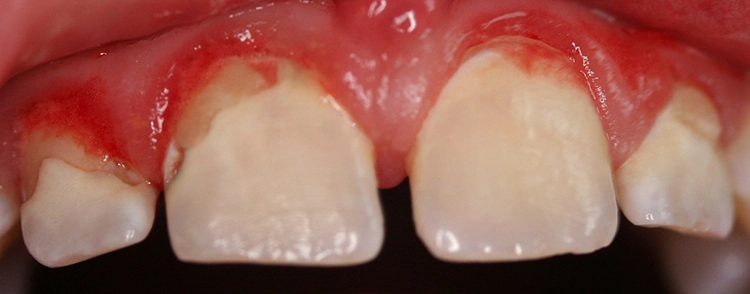

Ein 4-jähriges mäßig kooperatives Kind erscheint zur Kontrolle in der Zahnarztpraxis. Bei der klinischen Untersuchung sind offensichtlich zwei (scheinbar kleinere) approximal kavitierte kariöse Läsionen im Unterkiefer zu sehen sowie Läsionen an den Oberkieferschneidezähnen (Abb. 1a und b). Eine Versorgung dieser Zähne scheint nach klinischer Untersuchung bei diesem Kind noch ambulant möglich.

Dr. J. SchmoeckelAbb. 2: Die Frühkindliche Karies (früher „Nuckelflaschenkaries“ genannt) ist durch ein Auftreten flächiger kariöser Läsionen, die meist zunächst die Oberkieferschneidezähne betreffen, gekennzeichnet. Hauptursachen von ECC sind eine mangelhafte Zahnpflege beim Kleinkind in Kombination mit einem hochfrequenten Konsum zuckerhaltiger Getränke zwischendurch und/oder nachts.

Beim Kleinkind spielt primär die frühkindliche Karies eine Rolle, die initial meist durch kariöse Läsionen an den Oberkieferfrontzähnen gekennzeichnet ist (Abb. 2). Im permanenten Gebiss unterliegen die Kauflächen der durchbrechenden 1. und 2. Molaren insbesondere in der ca. 1,5 Jahre dauernden Durchbruchsphase einem erhöhten Kariesrisiko. Während kieferorthopädischer Maßnahmen mit festsitzenden Apparaturen bei Jugendlichen sollte besonderes Augenmerk auf die Beurteilung der Mundhygiene, wie dem Vorhandensein kariogener Plaque auf Kariesrisikoflächen (Abb. 3), und Kariesaktivität gelegt werden, um frühzeitig präventiv einzugreifen und klinische Bilder mit kariösen Läsionen an fast allen Zähnen möglichst zu vermeiden (Abb. 4).